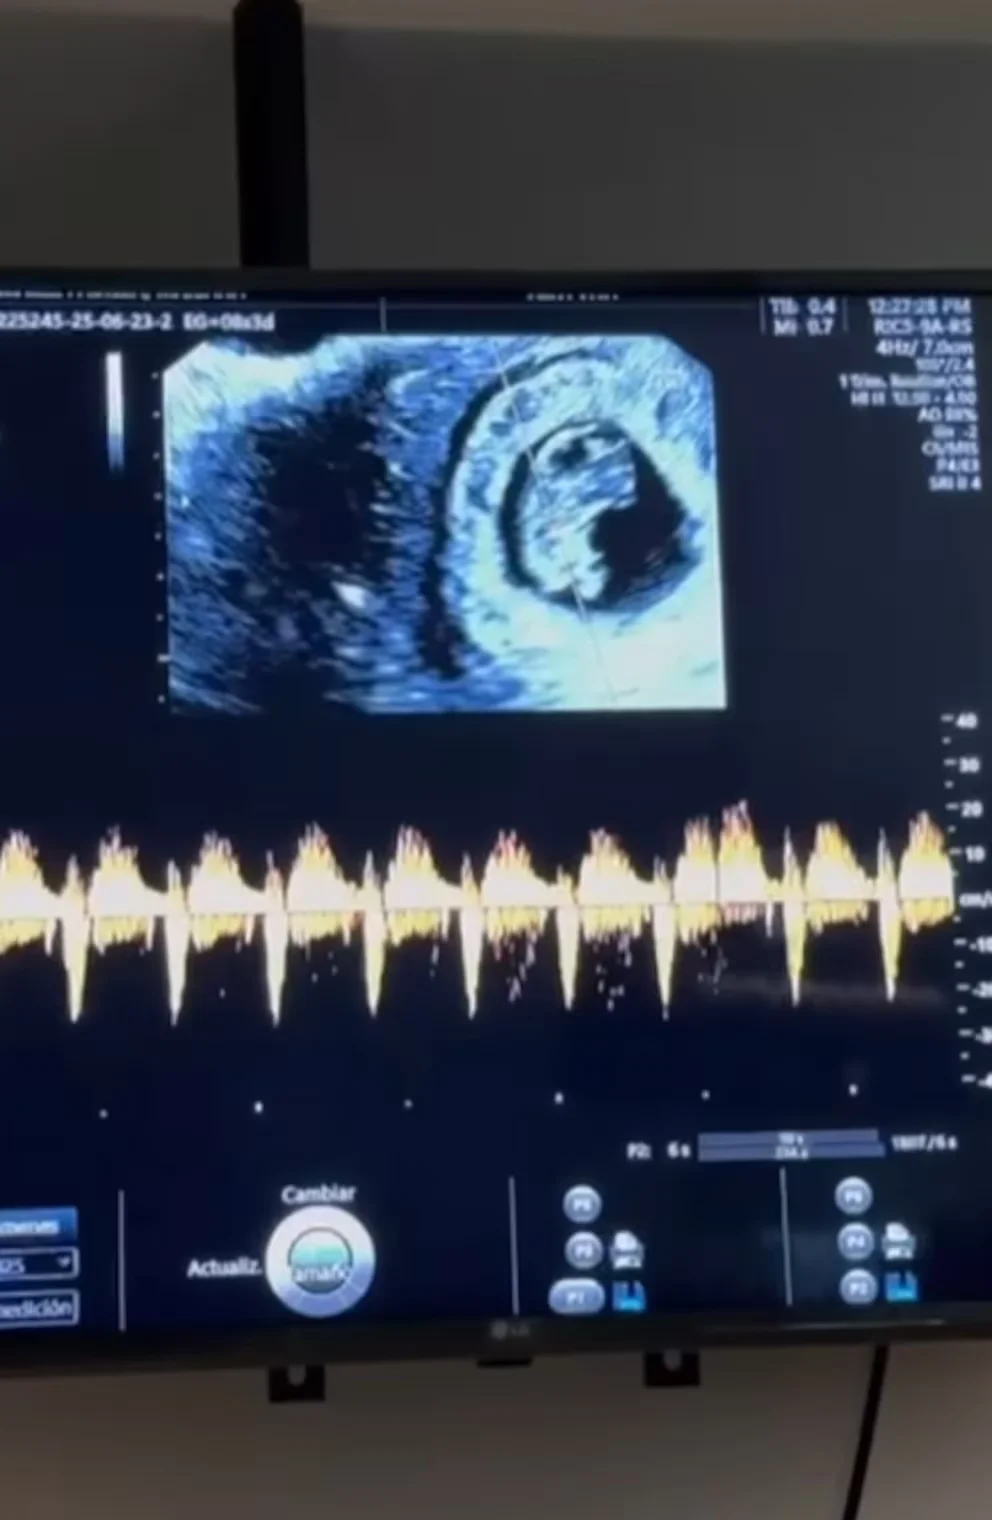

En un emotivo post en Instagram, Vicente Fernández Jr. y Mariana revelaron que el embarazo ya superó el primer trimestre. “No podíamos aguantar más las ganas de compartir esta alegría”, escribieron, acompañando el mensaje con imágenes de un ultrasonido y el latido del corazón del bebé. Aunque no han confirmado el sexo, la pareja expresó su ilusión por este “ser que nos une aún más”. Los fans llenaron la publicación con mensajes de apoyo, destacando la felicidad que refleja el matrimonio. “Qué bendición para la familia Fernández”, comentó un seguidor.